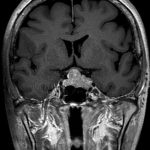

711

'25年12月

60代

良性頭蓋咽頭腫

頭蓋内腫瘍摘出術